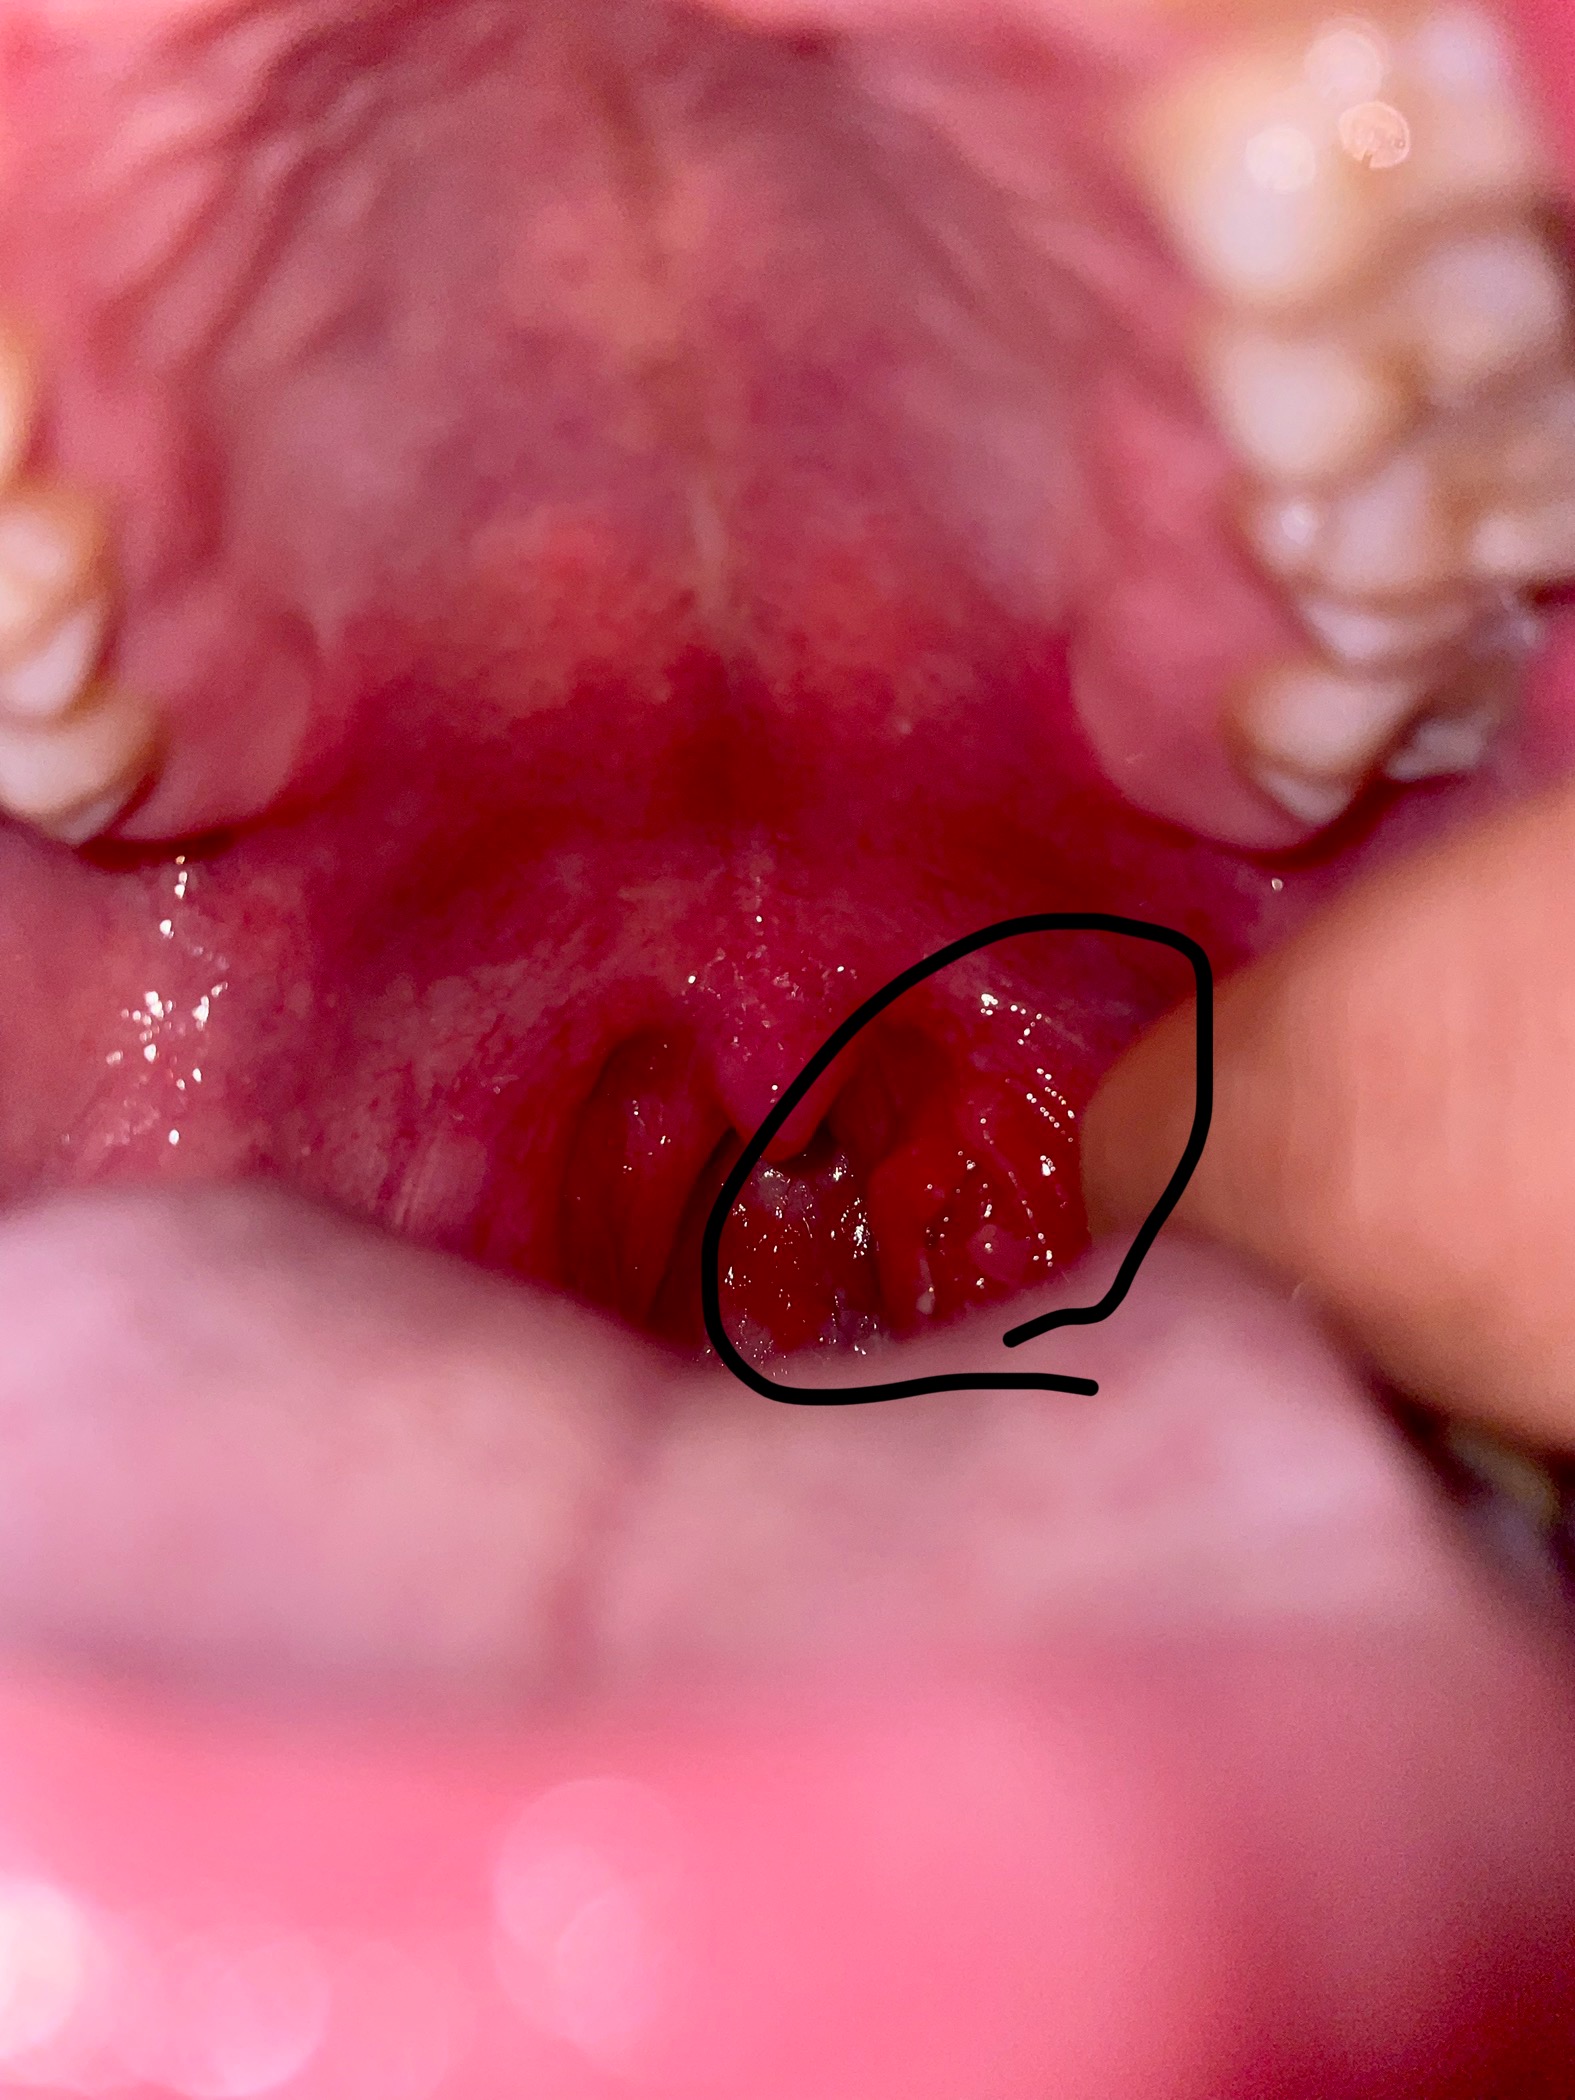

28 กรกฎาคม 2568 20:12:11 #1 มีติ่งเนื้อ 2-3 ติ่ง ที่ต่อมทอลซิลข้างซ้าย อีกข้างปกติ https://haamor.com/media/create_topic/20250728200842.jpeg https://haamor.com/media/create_topic/202507282008421.jpeg อยากทราบว่าเป็นติ่งเนื้ออะไร ผิดปกติไหมครับ |

30 กรกฎาคม 2568 13:02:05 #2 เป็นเนื้อของต่อมทอลซิลที่อักเสบจากการติดเชื้อครับ ควรไปพบแพทย์ครับ |